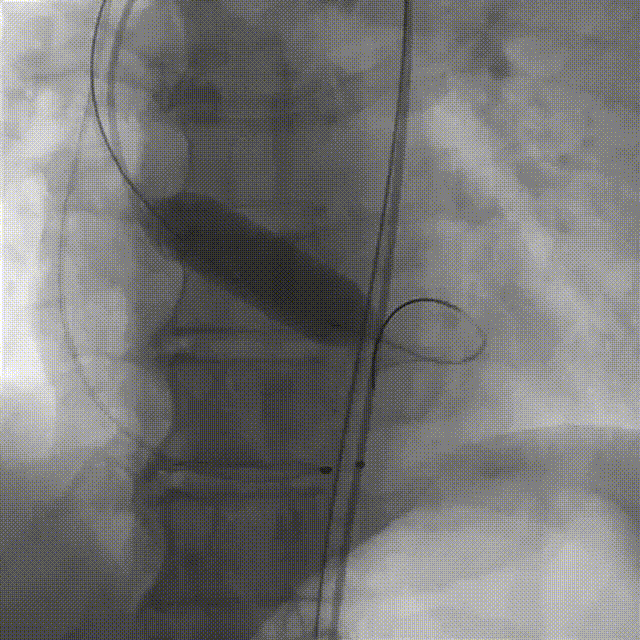

袁祖贻院长 西安交通大学第一附属医院 创新见证中国领跑,数据积累筑牢临床效果 韩克教授 西安交通大学第一附属医院 干瓣技术革新赋能特殊人群治疗,“量体裁衣”筑牢安全防线 患者病史 主诉与现病史:5年前因"血友病,血尿”就诊于当地医院,住院期间行心动超声提示主动脉瓣及二叶瓣畸形,无胸闷气短,无胸痛,咳嗽咳痰,无头晕,恶心呕吐等不适。未予以干预,后规律复查心超,3周前复查心超提示:主动脉瓣二瓣化畸形并重度狭窄,升主动脉内径明显增宽。 既往史:确诊血友病A型40年 术前超声提示:先天性主动脉瓣二叶式畸形,主动脉瓣中度狭窄,升主动脉增宽,左室舒张功能减低,EF73% 术前CT:Type0型二叶瓣,瓣叶增厚无钙化,主动脉瓣环径24.1mm,LVOT23.9mm;双侧冠脉开口高度可,窦部空间可,STJ、升主动脉内径可;预估冠脉低风险;主动脉水平夹角37.1°,主动脉弓角、弓距可;左室内径可;外周入路无明显迂曲,无钙化;双侧股动脉内径可,右侧股动脉低分叉。 手术策略 推荐右侧股动脉为主入路,左侧股动脉为辅入路。右股分叉上方1mm穿刺;仅舒张期时相,需根据球扩结果评估瓣膜尺寸,推荐使用18mm球囊进行预扩;预装AV26瓣膜。 手术过程 在右股动脉穿刺建立通路后,顺利送入大鞘。18mm球囊预扩后评估无腰无漏,后将Prostyle A® AV26瓣膜精准释放于目标位置,术后即刻造影显示无明显反流,无瓣周漏,平均跨瓣压差由术前的100mmHg降至2mmHg,患者血流动力学显著改善,术后超声证实瓣膜启闭良好。 主动脉根部造影 18球囊预扩 定位 稳定释放后脱钩 最终造影形态位置良好 外周血管造影,无血管并发症 术后超声显示无生物瓣位置固定瓣膜功能正常,无瓣周漏。 Prostyle A®预装干瓣——助力临床最优化解决方案 流入端桶状设计:流入端桶状的设计,锚定迅速,有效减少释放步骤,提升植入稳定性; 平衡的收腰设计:二叶瓣患者对瓣膜径向支撑力提出更高要求,Prostyle A®均衡的收腰设计可更好适应二叶瓣解剖,保证了EOA,有效降低了循环崩溃风险,提高瓣膜的耐久性; 预装干瓣 便捷顺安:金仕生物专利抗钙化技术运用纳米技术去除组织内的细胞碎片和磷脂,封闭游离醛基,从根本上阻断了瓣膜钙化的多项因素,显著提升了瓣膜的耐久性;同时,相比较传统戊二醛保存方式,干式存储最大限度的保留心包的亲水亲油平衡,还原组织天然曲柔性,进一步保障了瓣叶开合,保证长期耐久性。 专家简介 袁祖贻 西安交通大学第一附属医院(点击查看专家详细简历) 韩克 西安交通大学第一附属医院(点击查看专家详细简历) · END ·